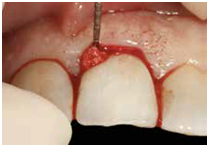

-軟組織區 (Fig 1,2)是指"植體與支台交界以上的區域" , 這個區域的組織若型態改變或變薄, 則內部的abutment將會透出顏色使組織變色 (abutment shine-through effect)

(Fig 1,2)

此案例是no.9(即左上正中門牙)有horizontal-oblique fracture的情形 (fig 5,6)

(Fig 5,6)